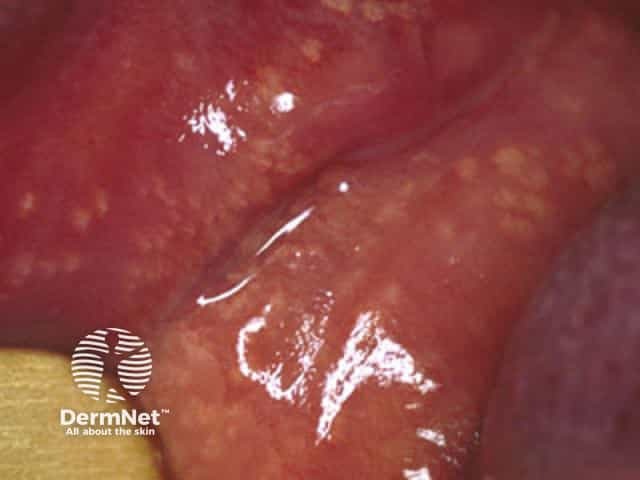

Fordyce spots are visible ectopic sebaceous (oil) glands without hair follicles located in the oral and/or genital mucosa. They are also called Fordyce granules.

Fordyce spots are small (1–5mm), slightly elevated yellowish or white papules that can appear on the inside of the cheeks and vermilion border of the lips, glans or shaft of the penis (Tyson glands), or the vulva and vagina of the female. Ectopic sebaceous glands can also occur on the areolae of the breasts where they are called Montgomery glands.

They may occur as a solitary lesion or more frequently in crops of about 50–100. They are easier to see when the skin is stretched.